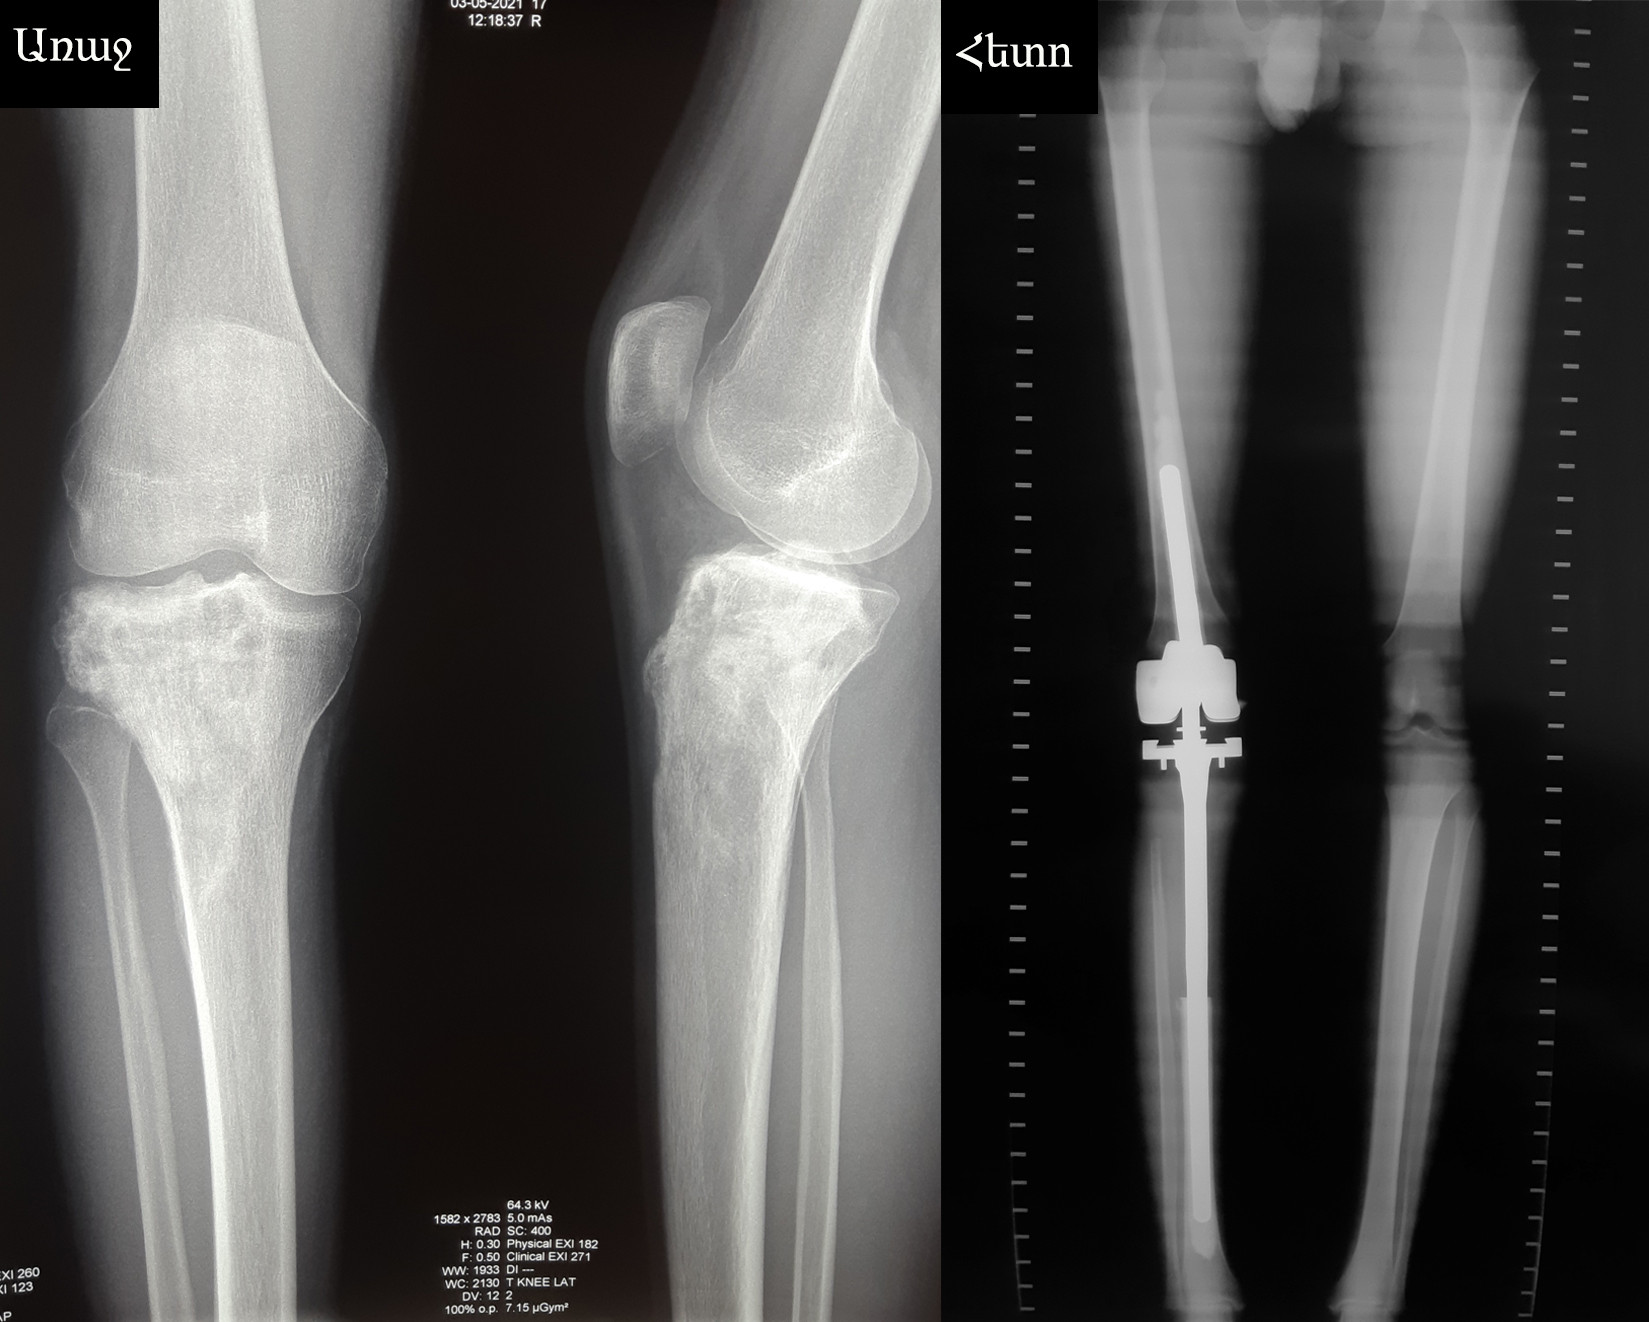

Կլինիկական դեպք. ոսկրահոդային դեֆեկտի անհատական էնդոպրոթեզավորում

Ախտորոշումը՝ աջ ոլոքի վերին երրորդականի օստեոսարկոմա:

Կատարվել է ոլոքի վերին երրորդականի և ծնկահոդի մասնահատում՝ ուռուցքի հեռացումով:

Առաջացած ոսկրահոդային դեֆեկտի անհատական էնդոպրոթեզավորում է կատարվել: